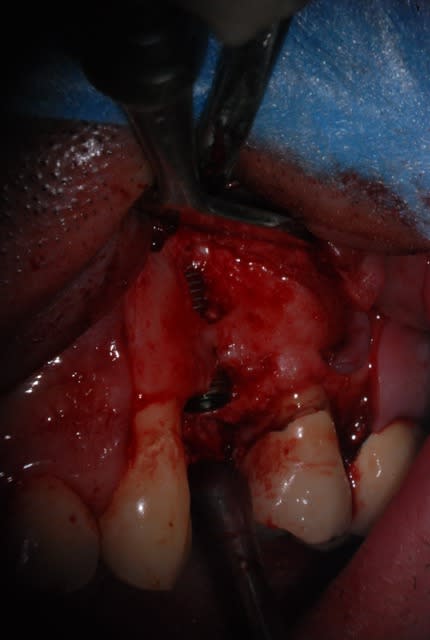

J'ai pas encore le scan

La corticale vestibulaire est présente sauf en regard de la lésion

L'occlusion est en classe I

Est ce que c'est raisonnable de faire une implantaion immédiate le jour de l'extraction avec un bon curetage de la lésion ?

T'as beaucoup de hauteur d'os au dessus de ta lesion, alors...pourquoi pas si t'es bon en largeur, et que tu garde des tissus mous en bon etats.

Tu peux envisager l'extraction implantation en curetant bien mais fais bien attention tu as apparamment aussi une lésion sur la dent adjacente.

Tu pourrais avoir un échec à cause de cette lésion que tu n'aura pas traitée et non pas à cause de ton extraction implantation.